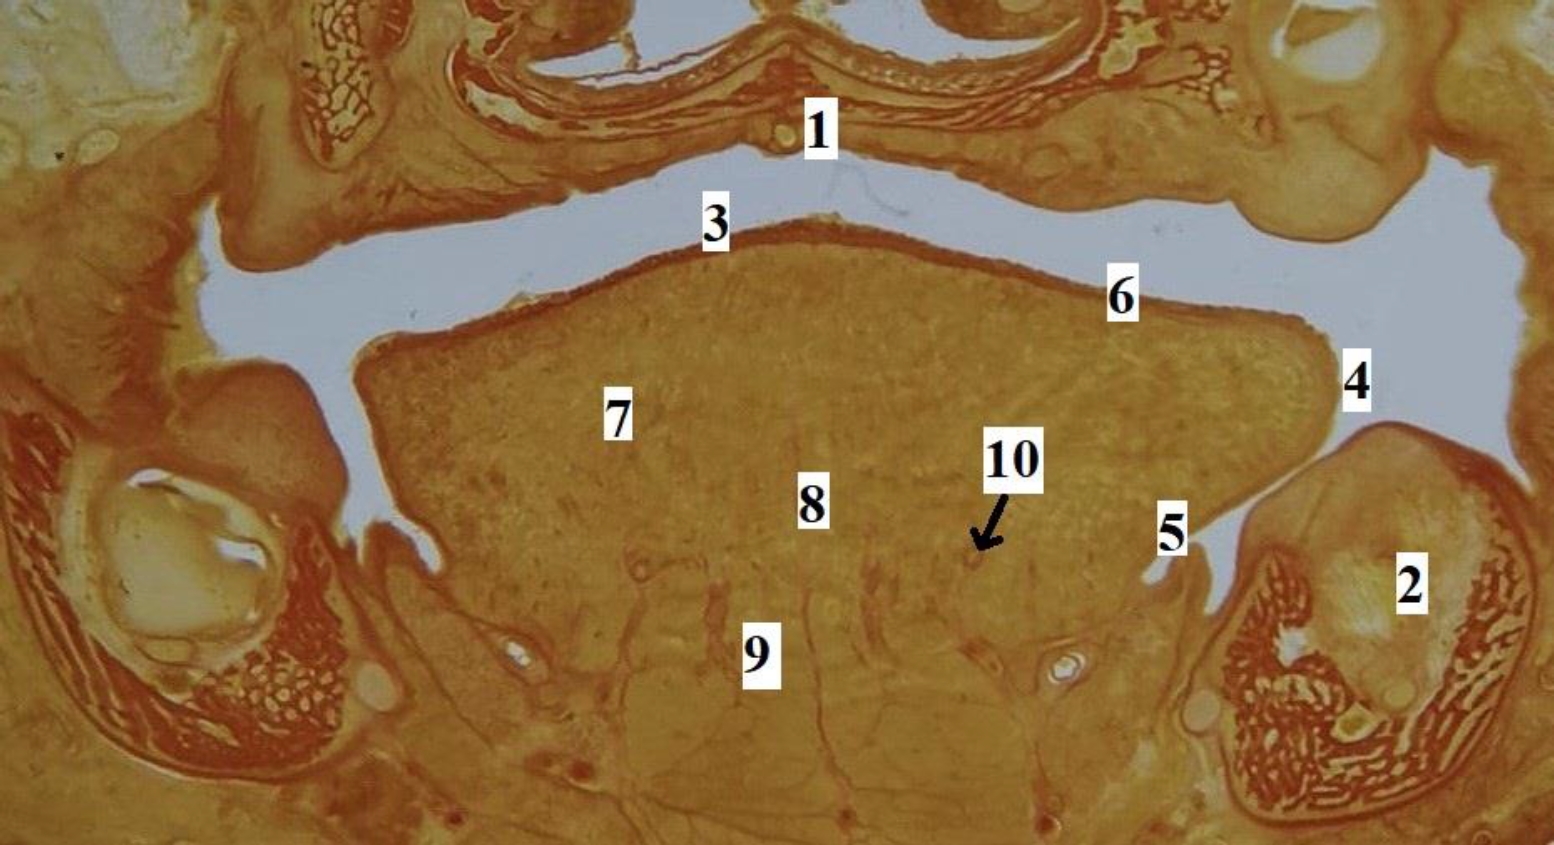

Рис. 3. Язык плода человека. Фронтальная гистотопограмма. Фото под микроскопом MicroOptix MX-1150, ок. ×10, об. 1. Возраст – 22 недели, пол мужской. Окраска по Ван – Гизону: 1 – твердое нёбо; 2 – нижняя челюсть; 3 – спинка языка; 4 – край языка; 5 – эпителий слизистой оболочки нижней поверхности языка; 6 – специализированный эпителий спинки языка; 7 – мышечные волокна поперечной мышцы языка; 8 – перегородка языка; 9 – мышечные волокна подбородочно-язычной мышцы; 10 – глубокая артерия языка

Язык человека в промежуточном плодном онтогенезе сформирован, макроскопически определяются все структурные элементы органа (рис. 2). На гистотопограммах визуализируется макромикроскопическая структура и микротопографические взаимоотношения мышц, сосудов, слизистой оболочки, стромального компонента языка (рис. 3). Линейные параметры языка, а также их описательная статистика представлены в табл. 2.

Рис. 2. Макропрепарат языка плода человека. Возраст – 17 недель, пол женский: 1 – слепое отверстие языка; 2 – пограничная борозда языка; 3 – спинка, предбороздовая часть тела языка; 4 – срединная борозда языка; 5 – край языка; 6 – верхушка языка; 7 – желобоватые сосочки языка; 8 – конусовидные, нитевидные, грибовидные сосочки языка